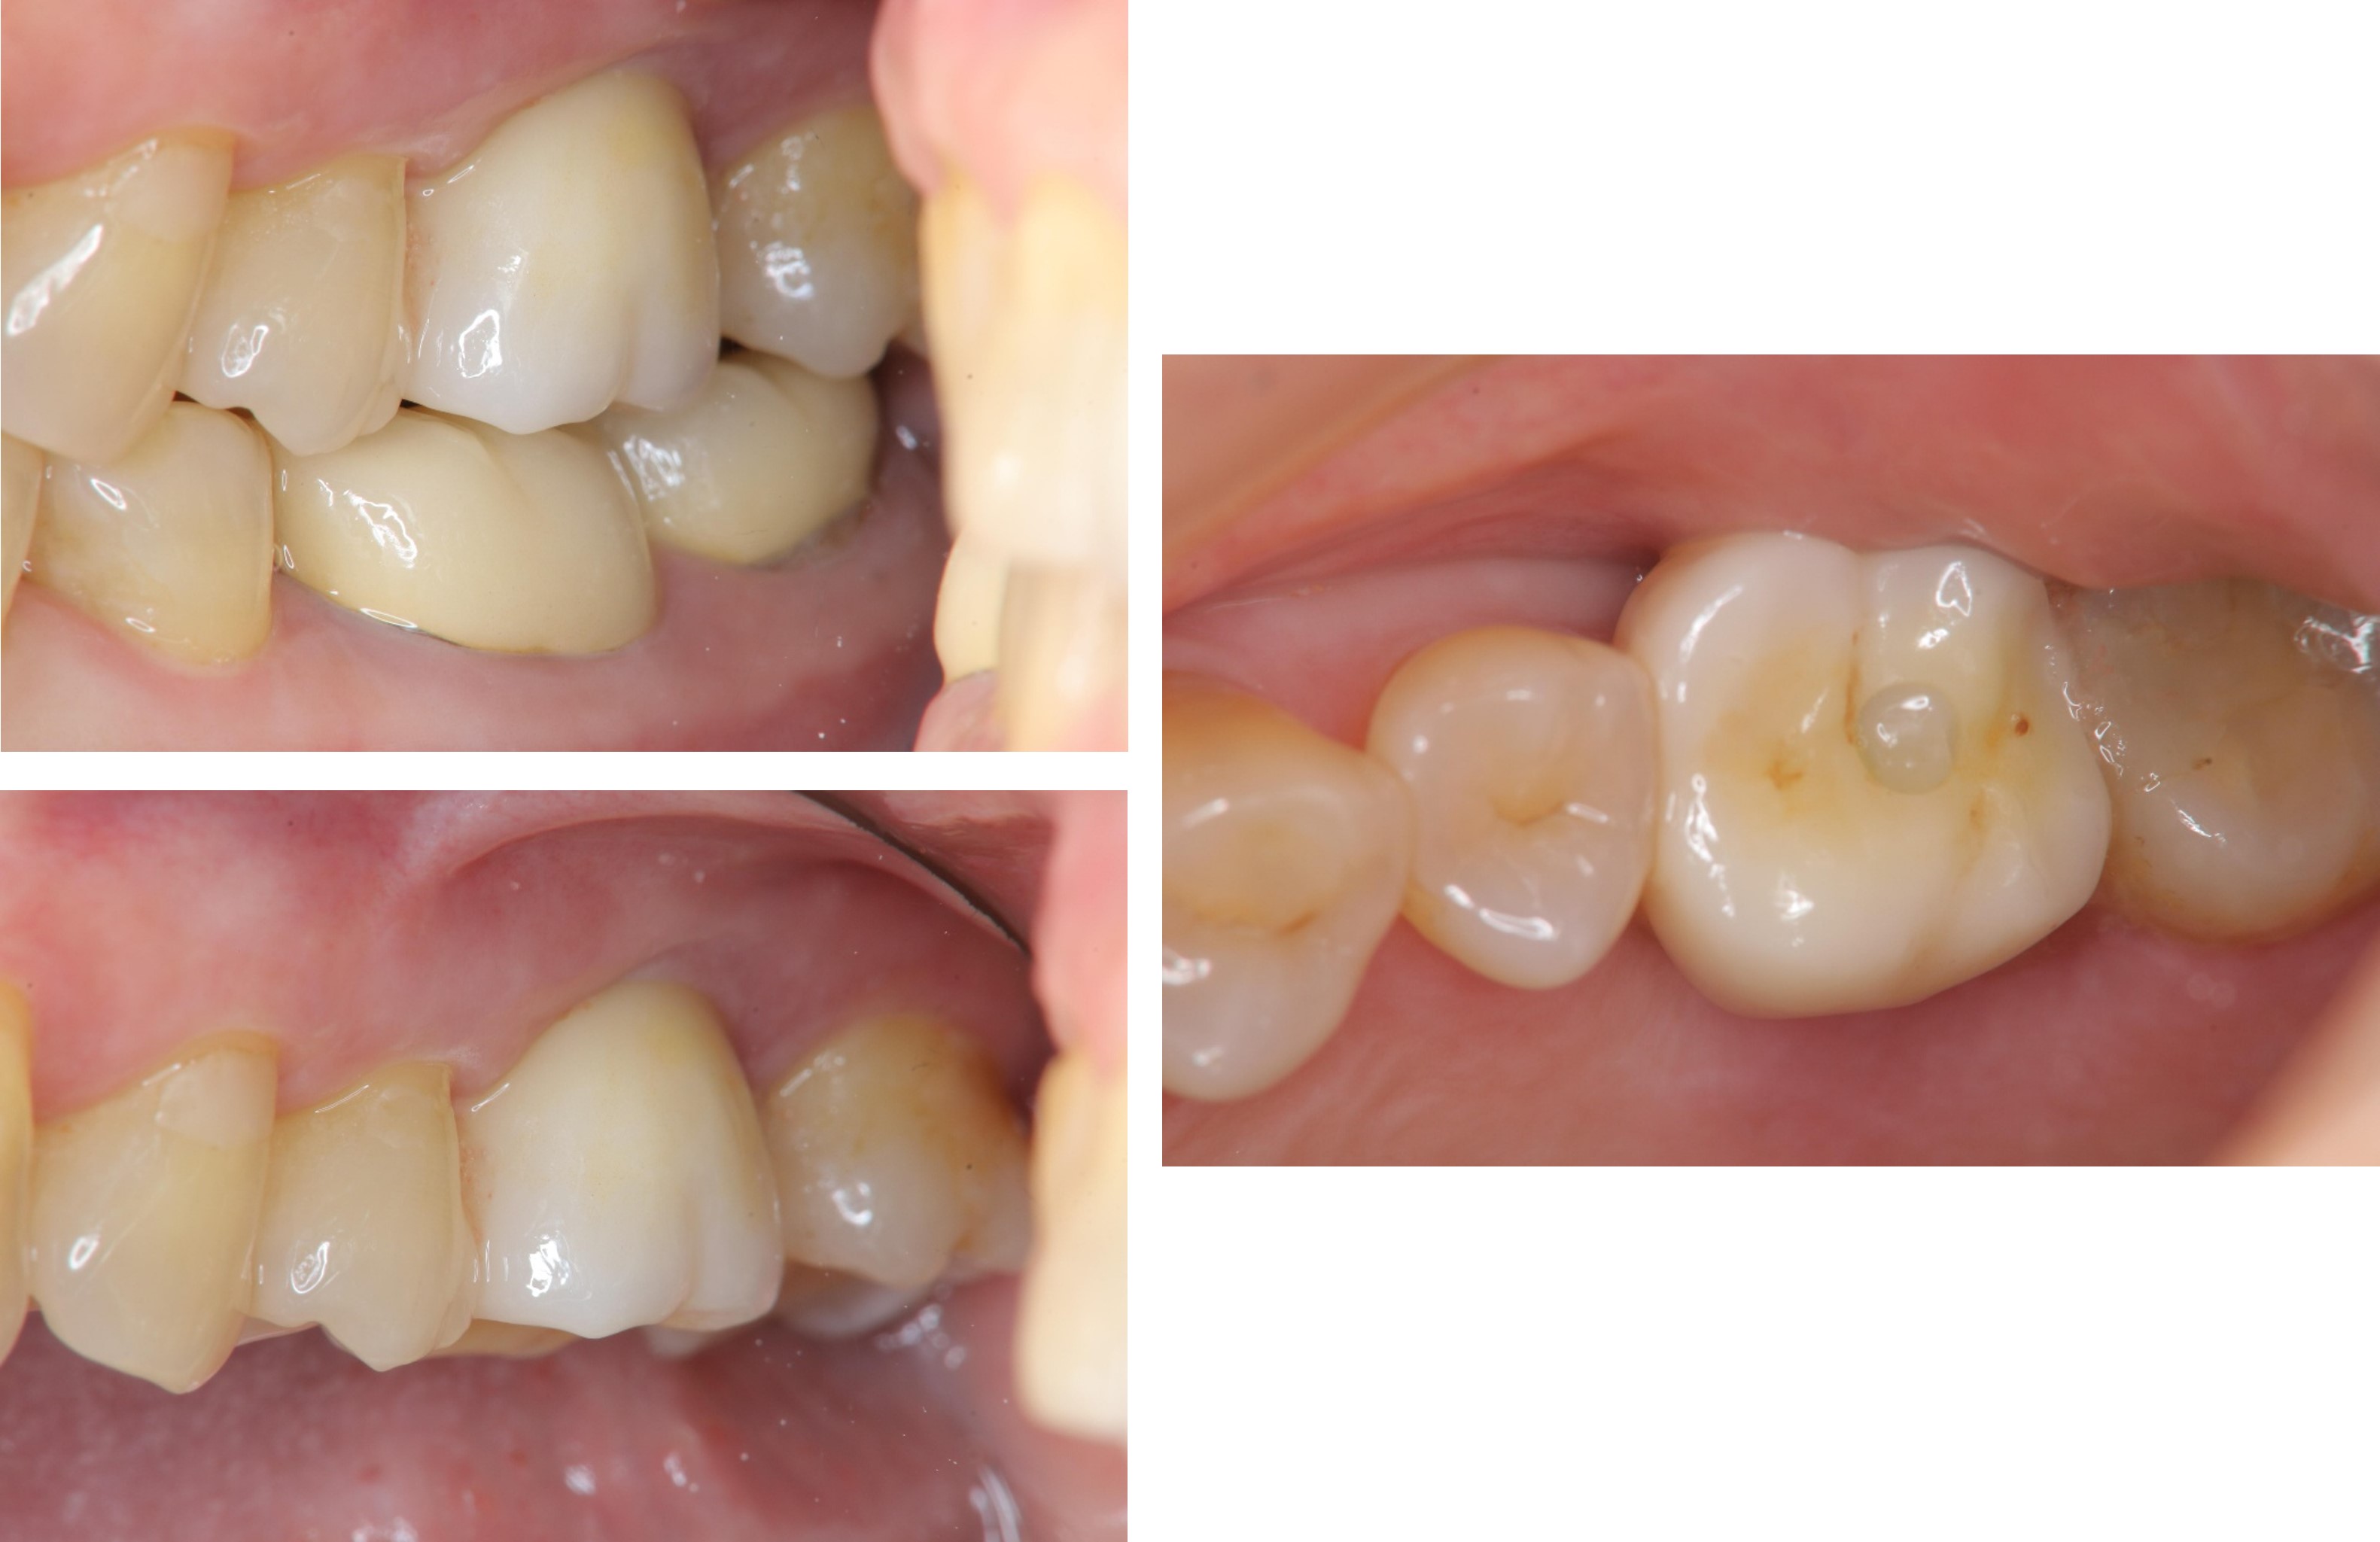

治療後,咬合牙周適應良好

治療後,密合度良好

術前、術後比較